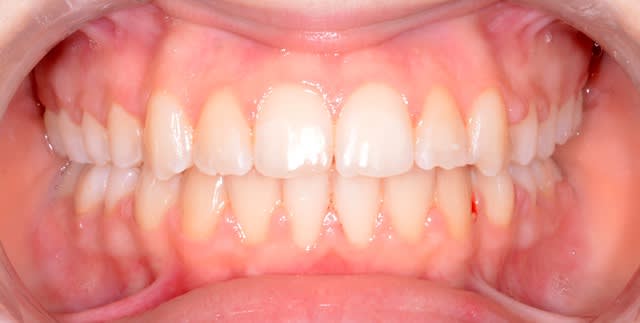

Apr s ndtyb1 - Eugenol

Bonjour à tous, patiente qui refuse catégoriquement l'implanto.

J'en ai bavé mais le résultat final est vraiment sympa.

Enfin la patiente et moi sommes très content.